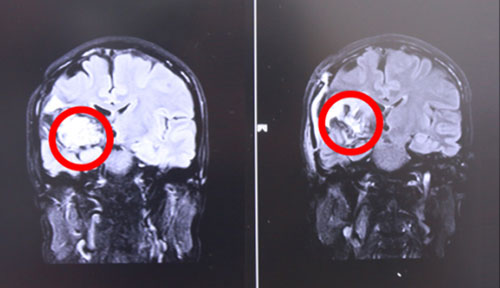

左侧为术前,右侧为术后,术后红圈内肿瘤物基本消失

17号上午9点左右,张XX被推入手术室,在全麻状态下接受“右颞顶海绵状血管瘤切除术”。至手术结束,已经日暮时分。手术由经验丰富的侯增欣主任主刀,上显微镜,分离侧裂,保护血管,切开颞上回皮质,见肿物呈暗褐色,靠近侧裂动脉,并向大脑深部丘脑生长,术中显微镜下肿物近全切除,手术顺利,脑神经及血管保护完好,患者全麻醒,返ICU病房进行术后监护。

术后,患者头晕症状好转,面部抽搐也未发作,肢体功能明显好转,生命体征平稳。据侯主任介绍,经过一段时间的康复,患者即可恢复生活自理能力。目前患者已经出院。针对此次案例,侯主任语重心长地说,作为一名神经外科医生,不仅要做好每一个手术,确保患者生命安全的前提下,尽可能全切肿瘤。更重要的是要针对每位患者的特殊情况特殊对待,拿捏好手术的度,不能一味保守或者冒进地对肿瘤不作为或不管不顾全切。侯主任根据自己临床多年的经验准确判断出病人损伤可以恢复,险中求稳求全,果断做了全切手术,从中我们也看到了一代专家的专业态度和敬业精神。